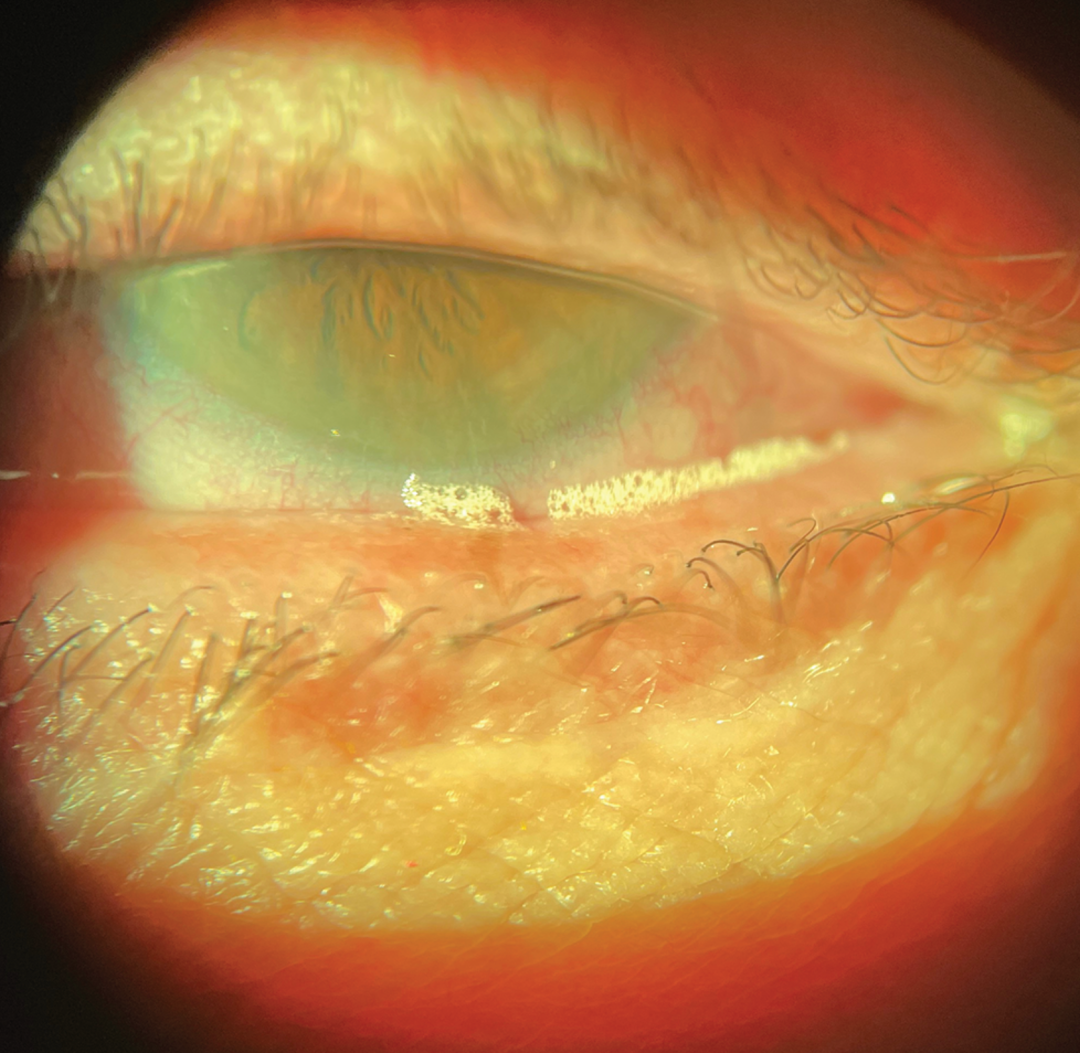

图5 蠕形螨感染出现在睫毛根部,患者向下凝视

睑缘炎是一种进行性慢性眼睑炎症性疾病,导致眼表刺激和继发性干眼症[58]。高达50%的慢性睑缘炎病例涉及寄生虫感染(如蠕形螨),通过睑板腺的机械阻塞、直接组织损伤和细菌过度生长加剧炎症[59-61]。蠕形螨通过其外骨骼、废物产物和促进微生物增殖引发免疫反应,形成炎症、腺体功能障碍甚至腺体丢失的循环[62、63]。蠕形螨感染也与眼酒渣鼻相关,表明存在共同的致病机制,如免疫失调或微生物群失调,这可能导致面部和眼部炎症表现。

我们现在有幸获得0.25%洛替拉纳滴眼液(Xdemvy,Tarsus Pharmaceuticals公司),这是一种选择性杀虫剂,通过诱导麻痹和死亡来靶向蠕形螨[64]。临床试验数据表明,每天两次使用六周可实现近乎完全的螨虫清除,并显著减少睫毛周围的袖套样改变[65]。通过消除寄生虫负担,洛替拉纳破坏了炎症级联反应,使腺体功能和泪膜稳定性得以恢复,使患者能够体验到睑缘炎症和瘙痒、灼烧等症状的减轻[66]。

最近的研究表明,洛替拉纳可能有助于管理与蠕形螨睑缘炎相关的睑板腺功能障碍,在第85天使产生液体分泌的睑板腺数量增加78%,并在波动视力、灼烧、瘙痒和发红方面有统计学显著改善。